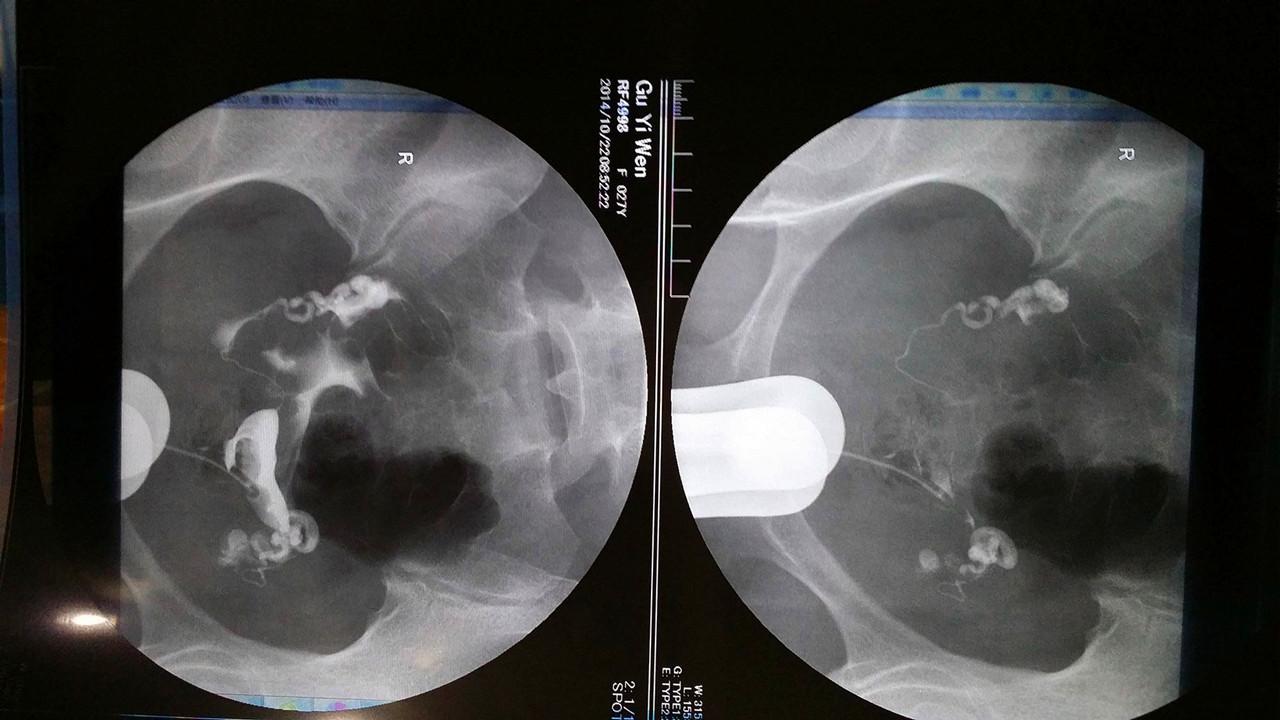

的懂片子吗,做照影时拍的,检查说是通而不畅,一年都过去了,还是没怀孕

广西工人医院x光子宫输卵管造影照片